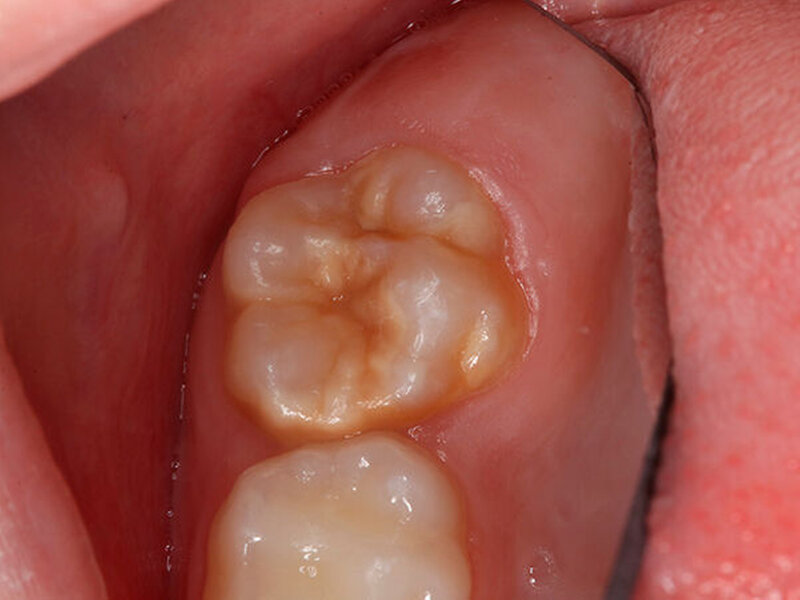

Eine einheitliche Leitlinie für die Behandlung der MIH gibt es bislang noch nicht. Wissenschaftler der European Academy of Paediatric Dentistry (EAPD) haben jedoch 2010 einen klinischen Fahrplan zur Behandlung der MIH präsentiert,(3) demzufolge zunächst geklärt werden sollte, ob es sich um eine milde oder schwere Ausprägung handelt - im weiteren werden die Hypersensitivitäten betrachtet. Bei der leichten Form der MIH reichen Präventionsmaßnahmen in der Zahnarztpraxis oder zu Hause in der Regel aus. Für die häusliche Anwendung eignen sich GC Tooth Mousse (ohne Fluorid) und MI Paste Plus. Beide Produkte enthalten den Wirkstoff Recaldent, der die Remineralisierung der Zähne fördert und den Zahnschmelz stärkt. Hypersensible Zähne werden damit drei Monate lang morgens und abends drei Minuten vor dem Zähneputzen für 30 Sekunden behandelt. Mit dem Fluoridlack MI Varnish werden sowohl bei milder als auch schwerer MIH die Dentintubuli in der Zahnarztpraxis nach der Prophylaxe versiegelt. Beide Maßnahmen in der Praxis und zu Hause können die Empfindlichkeit der MIH-Zähne reduzieren.

Bei einer schweren MIH können kleinere Fissuren einfach und schnell mit dem flüssigen Glasionomer-Oberflächenschutzmaterial GC Fuji Triage zum Schutz vor Karies abgedeckt werden. Das Verfahren ist für die Patienten schmerzlos und minimalinvasiv. Bereits eingetretene, größere Defekte können mit den Füllungsmaterialien EQUIA Fil (Glasionomer) und EQUIA Forte HT (hochviskoses Glas-Hybrid) versorgt werden. In einigen Fällen ist bei einer schweren MIH eine definitive Füllung aufgrund des Defektes nicht möglich. Hierfür eignet sich ergänzend zu Glasionomeren die Behandlung der Überkappung mit Edelstahlkronen, die zudem mit Glasionomer befestigt werden. Sie dient als Übergangslösung, bis eine definitive Versorgung durch eine indirekte Restauration möglich ist.

Wichtig für den Therapieerfolg ist ein (engmaschiger) Recall, denn MIH-Patienten sollten u.a. aufgrund der höheren Kariesanfälligkeit intensiver kontrolliert und nachbehandelt werden. Dazu zählen sowohl die regelmäßige Kontrolle der Restaurationen als auch die sorgfältige häusliche Mundhygiene. Für den Behandlungserfolg ist die Therapietreue bei der Anwendung der remineralisierenden Materialien entscheidend.